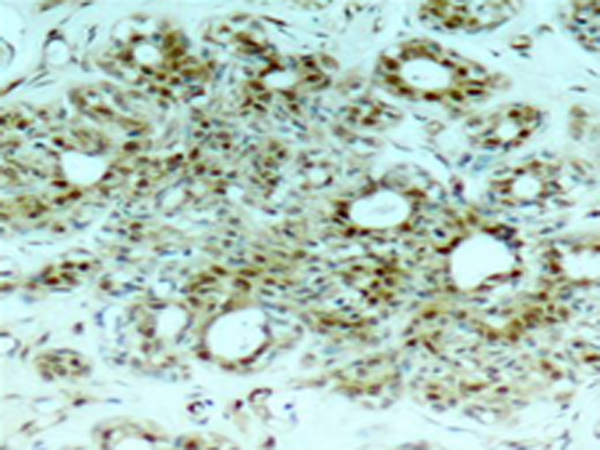

IHC positive control:

Human breast carcinoma tissue

IHC Recommend dilution:

50-100